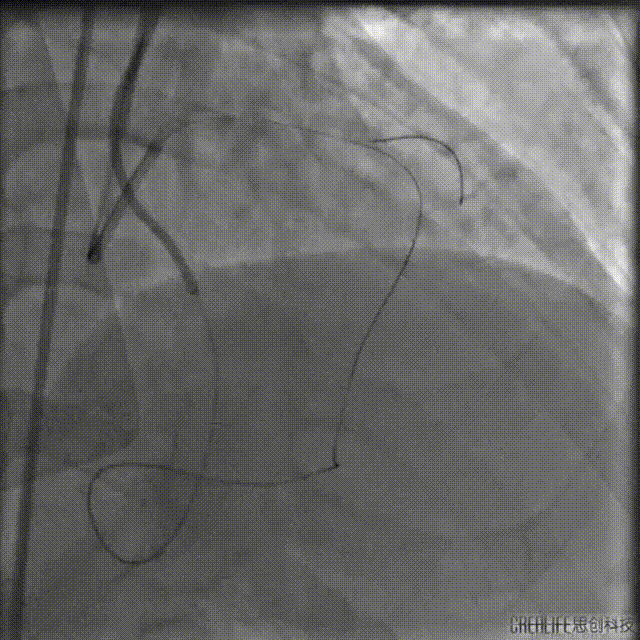

2.5*15mm球囊后扩时球囊发生断裂,导丝旋转缠绕后撤出左侧指引导管。

球囊杆断裂的处理方法:

断端在GC内:球囊断开的软段还在GC内,选择再送入导丝和球囊锚定后撤出。

断端在升主动脉:使用抓捕器,尤其断裂段在升主动脉,球囊断端以远没有坚硬的部位,紧紧抓住后收到GC内也是很好的方法,注意精细操作抓捕。

断端在冠脉内:选择抓捕法或导丝缠绕法,这两种方法的困难点在于把导丝通过球囊送到远端,其中抓捕法应该比较难实现,在近段可以进行尝试,选择自制抓捕器,同时使用延长导管辅助抓捕。对于缠绕法,需考虑导丝从支架中心腔通过的问题,还包括导丝能否顺利缠绕,能否顺利回拉,延长导管能否成功跨过血管近段病变跟入等等困难。

IVUS查看见支架远端局部血肿,遂远段植入2.25*29mm支架,并送入2.5*15mm球囊后扩,并用4.0*12mm球囊后扩近段支架。

最终造影结果

复查造影未见明显狭窄,TIMI血流3级。